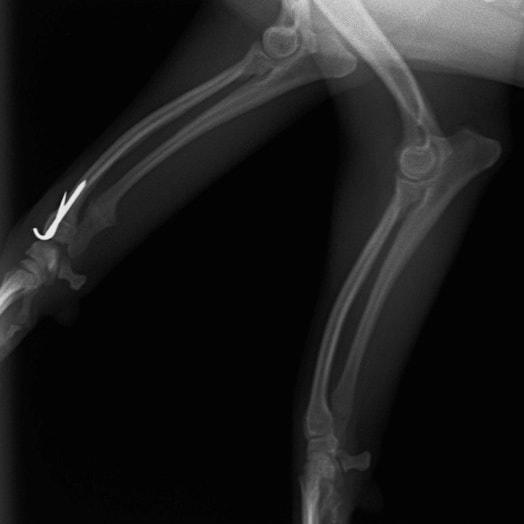

症例3:キルシュナーワイヤーのピンニングによる整復

ペルシャ猫 11ヶ月齢 雄

他院にて左大腿骨遠位の成長板骨折(salter-harrisⅠ型)が認められており、治療相談を目的として来院。当院にて、キルシュナーワイヤーを用いたピンニングにより骨折部位の整復を行いました。術後の経過は良好で、現在も経過観察中です。

術前レントゲン

術後レントゲン

Arthrex社のターゲティングデバイスを用いてピンニングの位置を調整することで、確実な固定を行っています。当院ではこの手術器具以外にも、人の手術にも使用される様々な器具を導入し、手術精度を高め、また医療メーカーと新しい器具の開発、試作にも取り組んでおります。